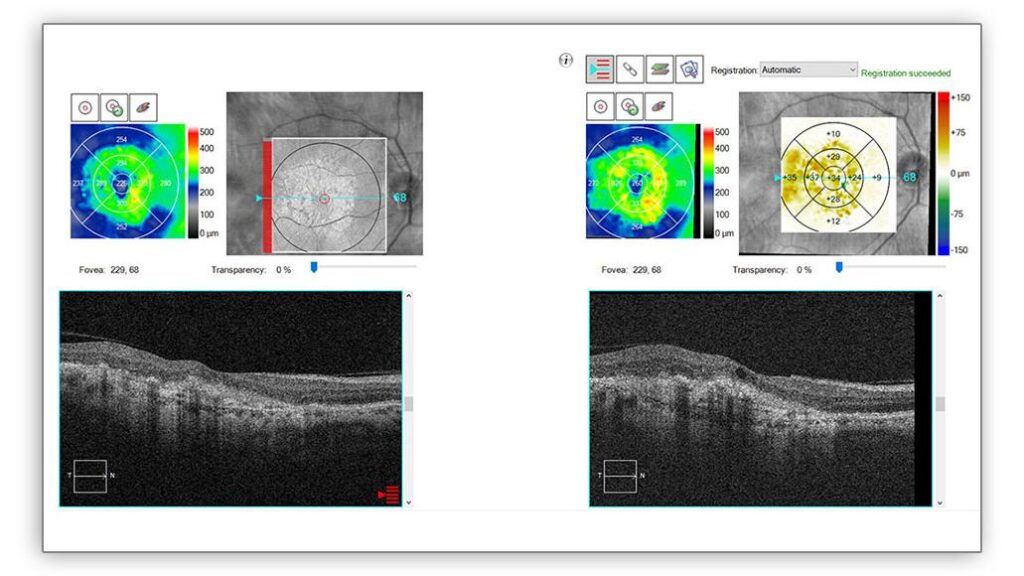

The device now offers wider and deeper OCT/OCTA scans. It features 12 mm × 12 mm OCT angiography and a B-scan depth of up to 2.9 mm. The release said the HD AngioPlex scan provides more detail than previous models.

- High-Definition Imaging: HD OCT and OCT Angiography (OCTA) capture the finest microvascular details of the retina. The CIRRUS 6000 shows the detailed structures and problems of the retina, which is important for good patient care.

- Proven Analytics for Smart Decisions: The CIRRUS platform uses clinically validated applications. These help with accurate analysis and quicker decision-making. This applies to many conditions, such as retina, glaucoma, and anterior segment.

- Comprehensive Reference Database: The larger ZEISS CIRRUS Reference Database has data from 870 patients. This creates a solid foundation for comparing measurements, including macular thickness, ganglion cell thickness, optic disc thickness, and RNFL. We can compare these measurements to a reference range for healthy eyes.